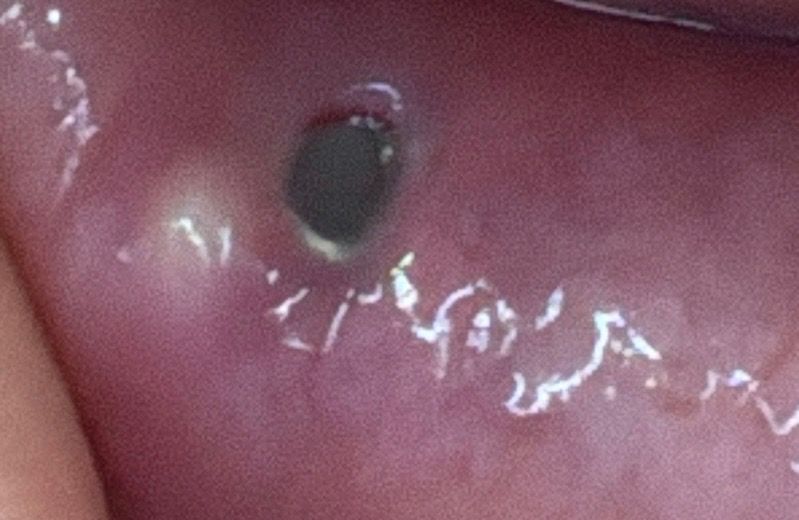

저번 주 금요일 피어싱 교체를 하며 입술 안쪽에서 동그란게 느껴졌습니다 그리고 오늘 월요일 거울로 확인을 해보니 뾰루지처럼 단단하게 올라온 노란 무언가가 있는데 병원 가서 짜내야 하는지 자연스럽게 터지기도 하는 건지 궁금합니다!

통증은 건드리면 약간 쓰리지만 평상 시 생활할 땐 모를 정도로 크지 않습니다

• 1번 째 사진